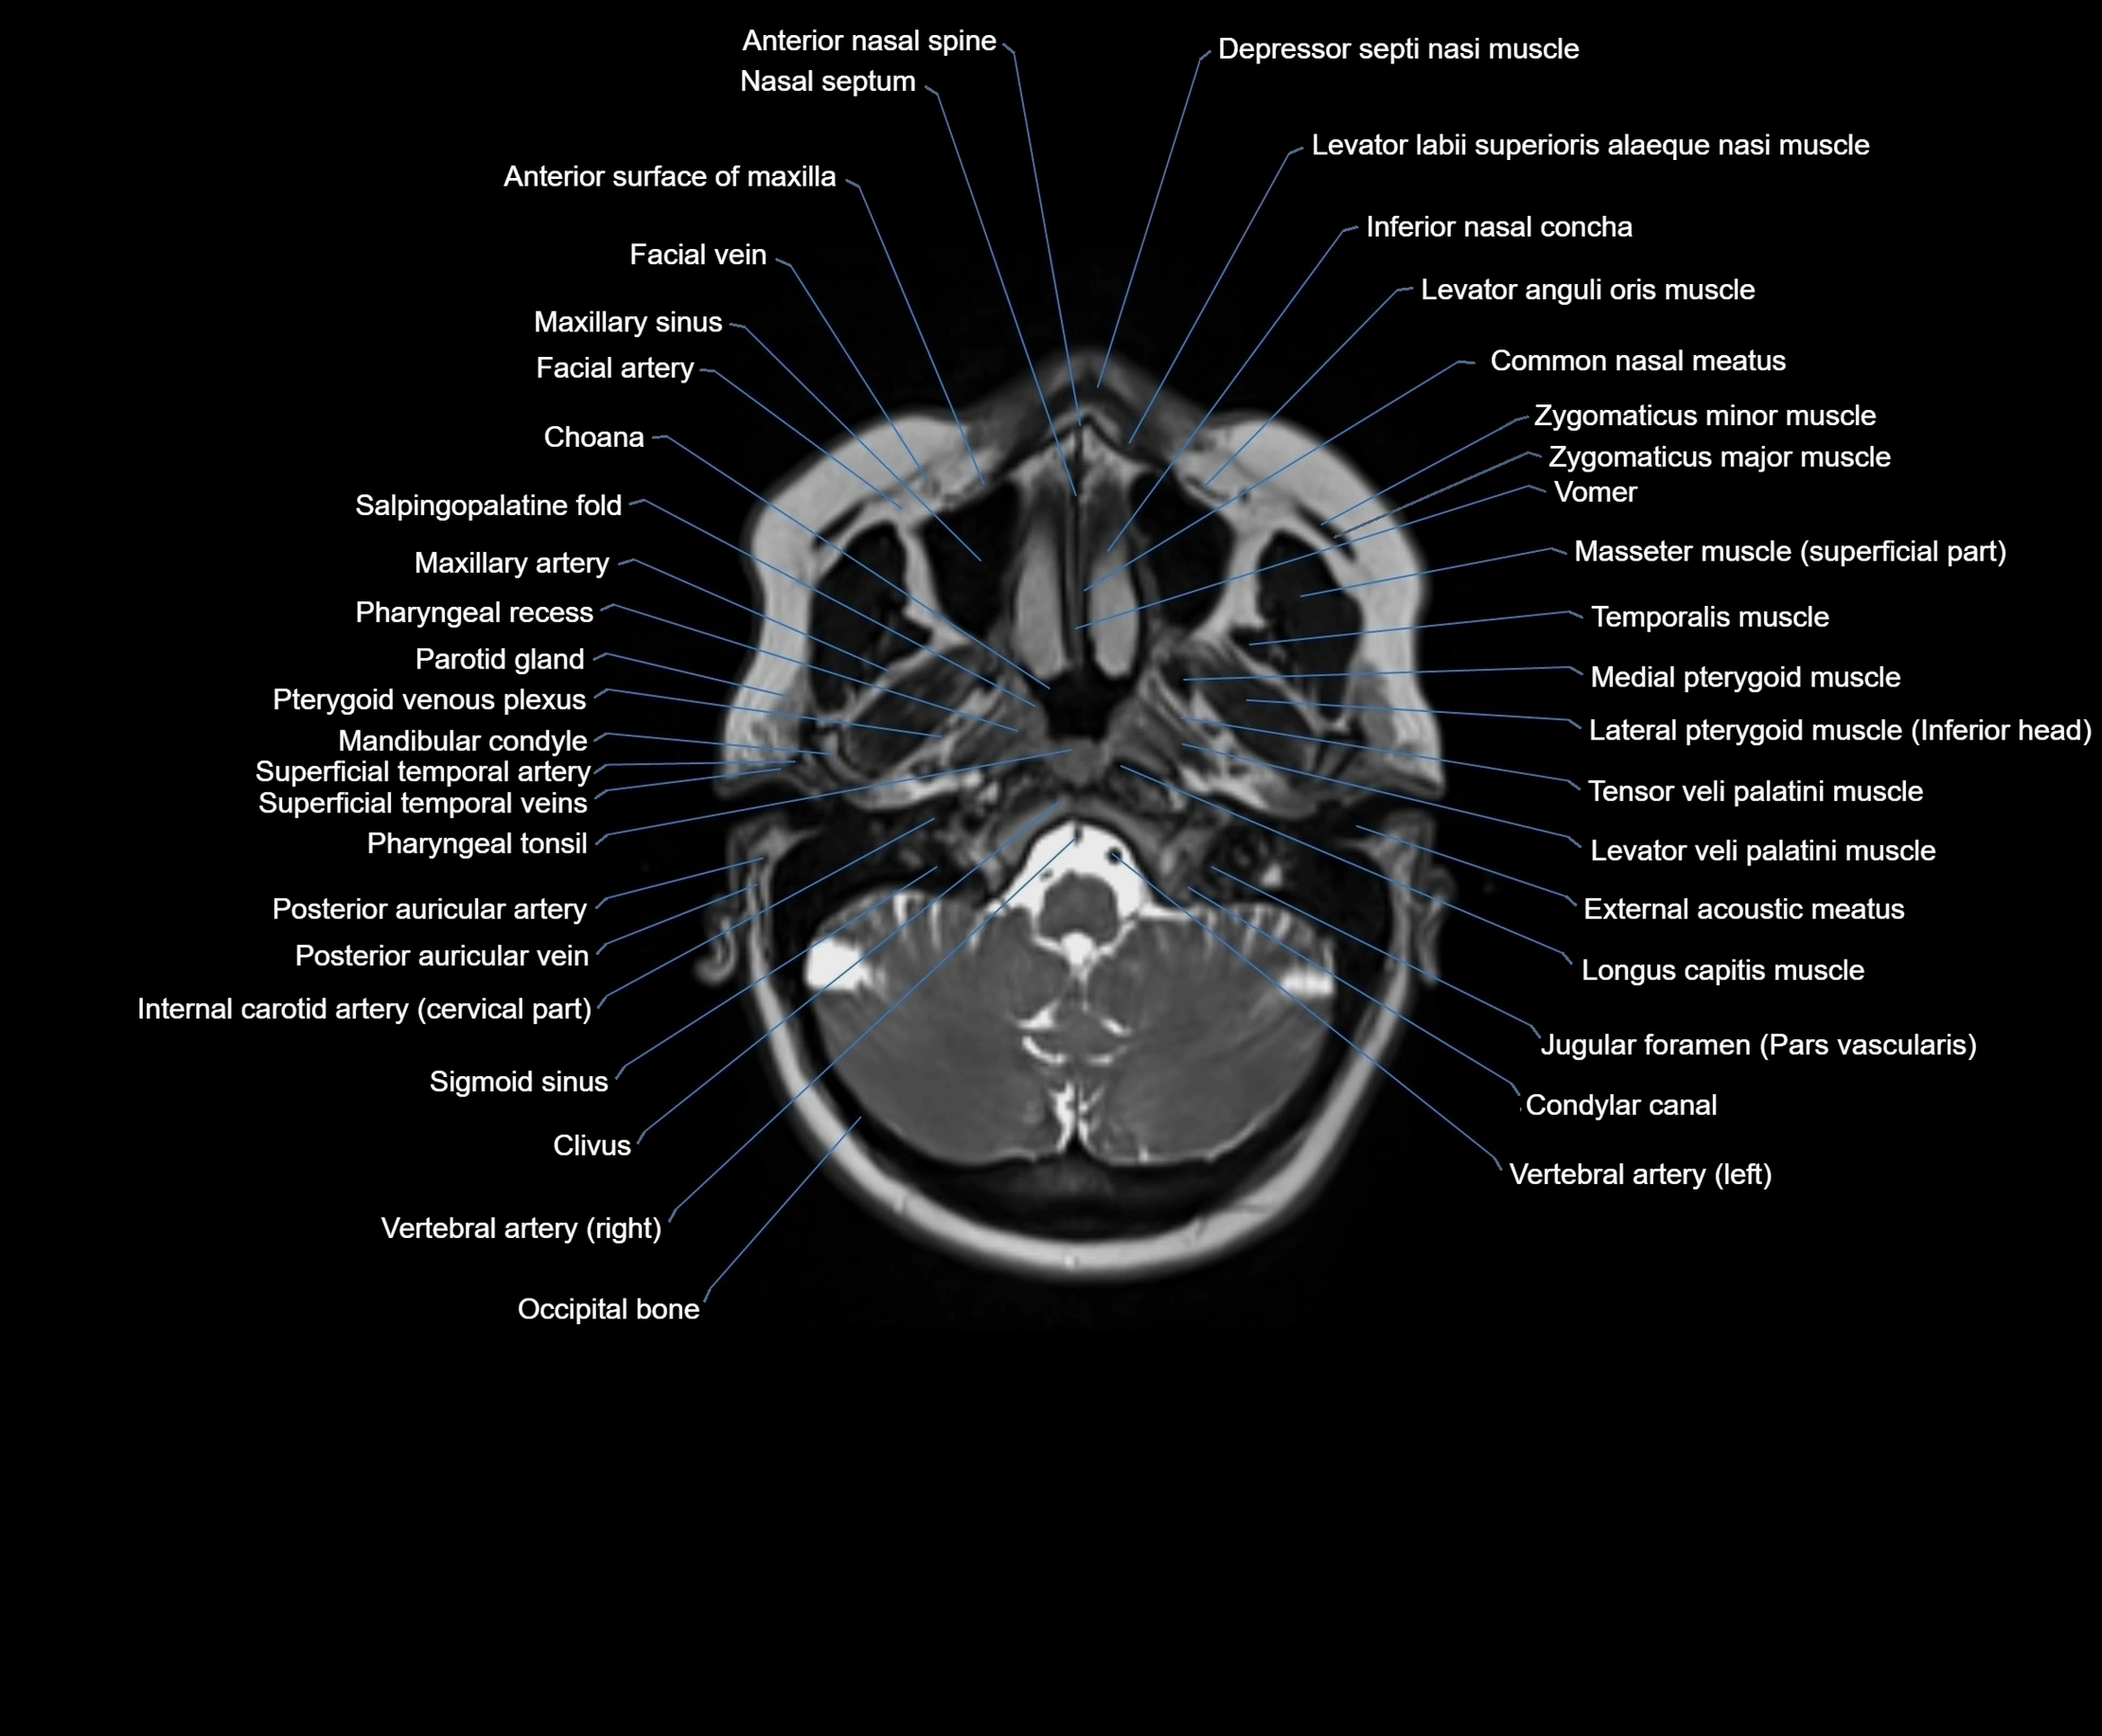

- Choana

- Clivus

- Common nasal meatus

- Condylar canal

- External acoustic meatus

- Inferior nasal concha

- Internal carotid artery (cervical part)

- Jugular foramen pars vascularis

- Levator veli palatini muscle

- Longus capitis muscle

- Mandibular condyle

- Maxillary artery

- Maxillary sinus

- Occipital bone

- Parotid gland

- Pharyngeal tonsil

- Posterior auricular artery

- Posterior auricular vein

- Pterygoid venous plexus

- Sternocleidomastoid muscle

- Superficial temporal artery

- Superficial temporal vein

- Temporalis muscle

- Tensor veli palatini muscle

- Vomer